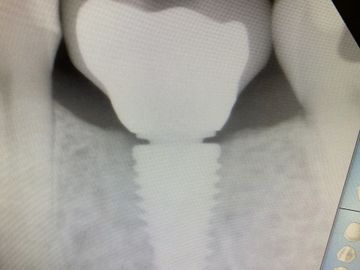

Send an X-ray to the LAB so they know where the implant is in relation to bone. This x-ray above shows the tussie measurement gauge finger tightened down on implant.

Tissue Measurement Gauge: In both surgical and restorative kits. The black lines indicate different tissue hieghts that match our healing abutment heights and the margins on our abutments.

the yellow lines on the xray indicate that both a 1.5 and 2.5 gignival margin on abutment would work for margin height selection of abutment.

even on xray can see notches on side of tissue gauge

read tool at top of tissue, then select margin of abutment 1-2 mm subgingival